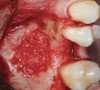

Fig 10. Small Schneiderian membrane perforation (arrow) during a standard lateral approach.

Figure 10